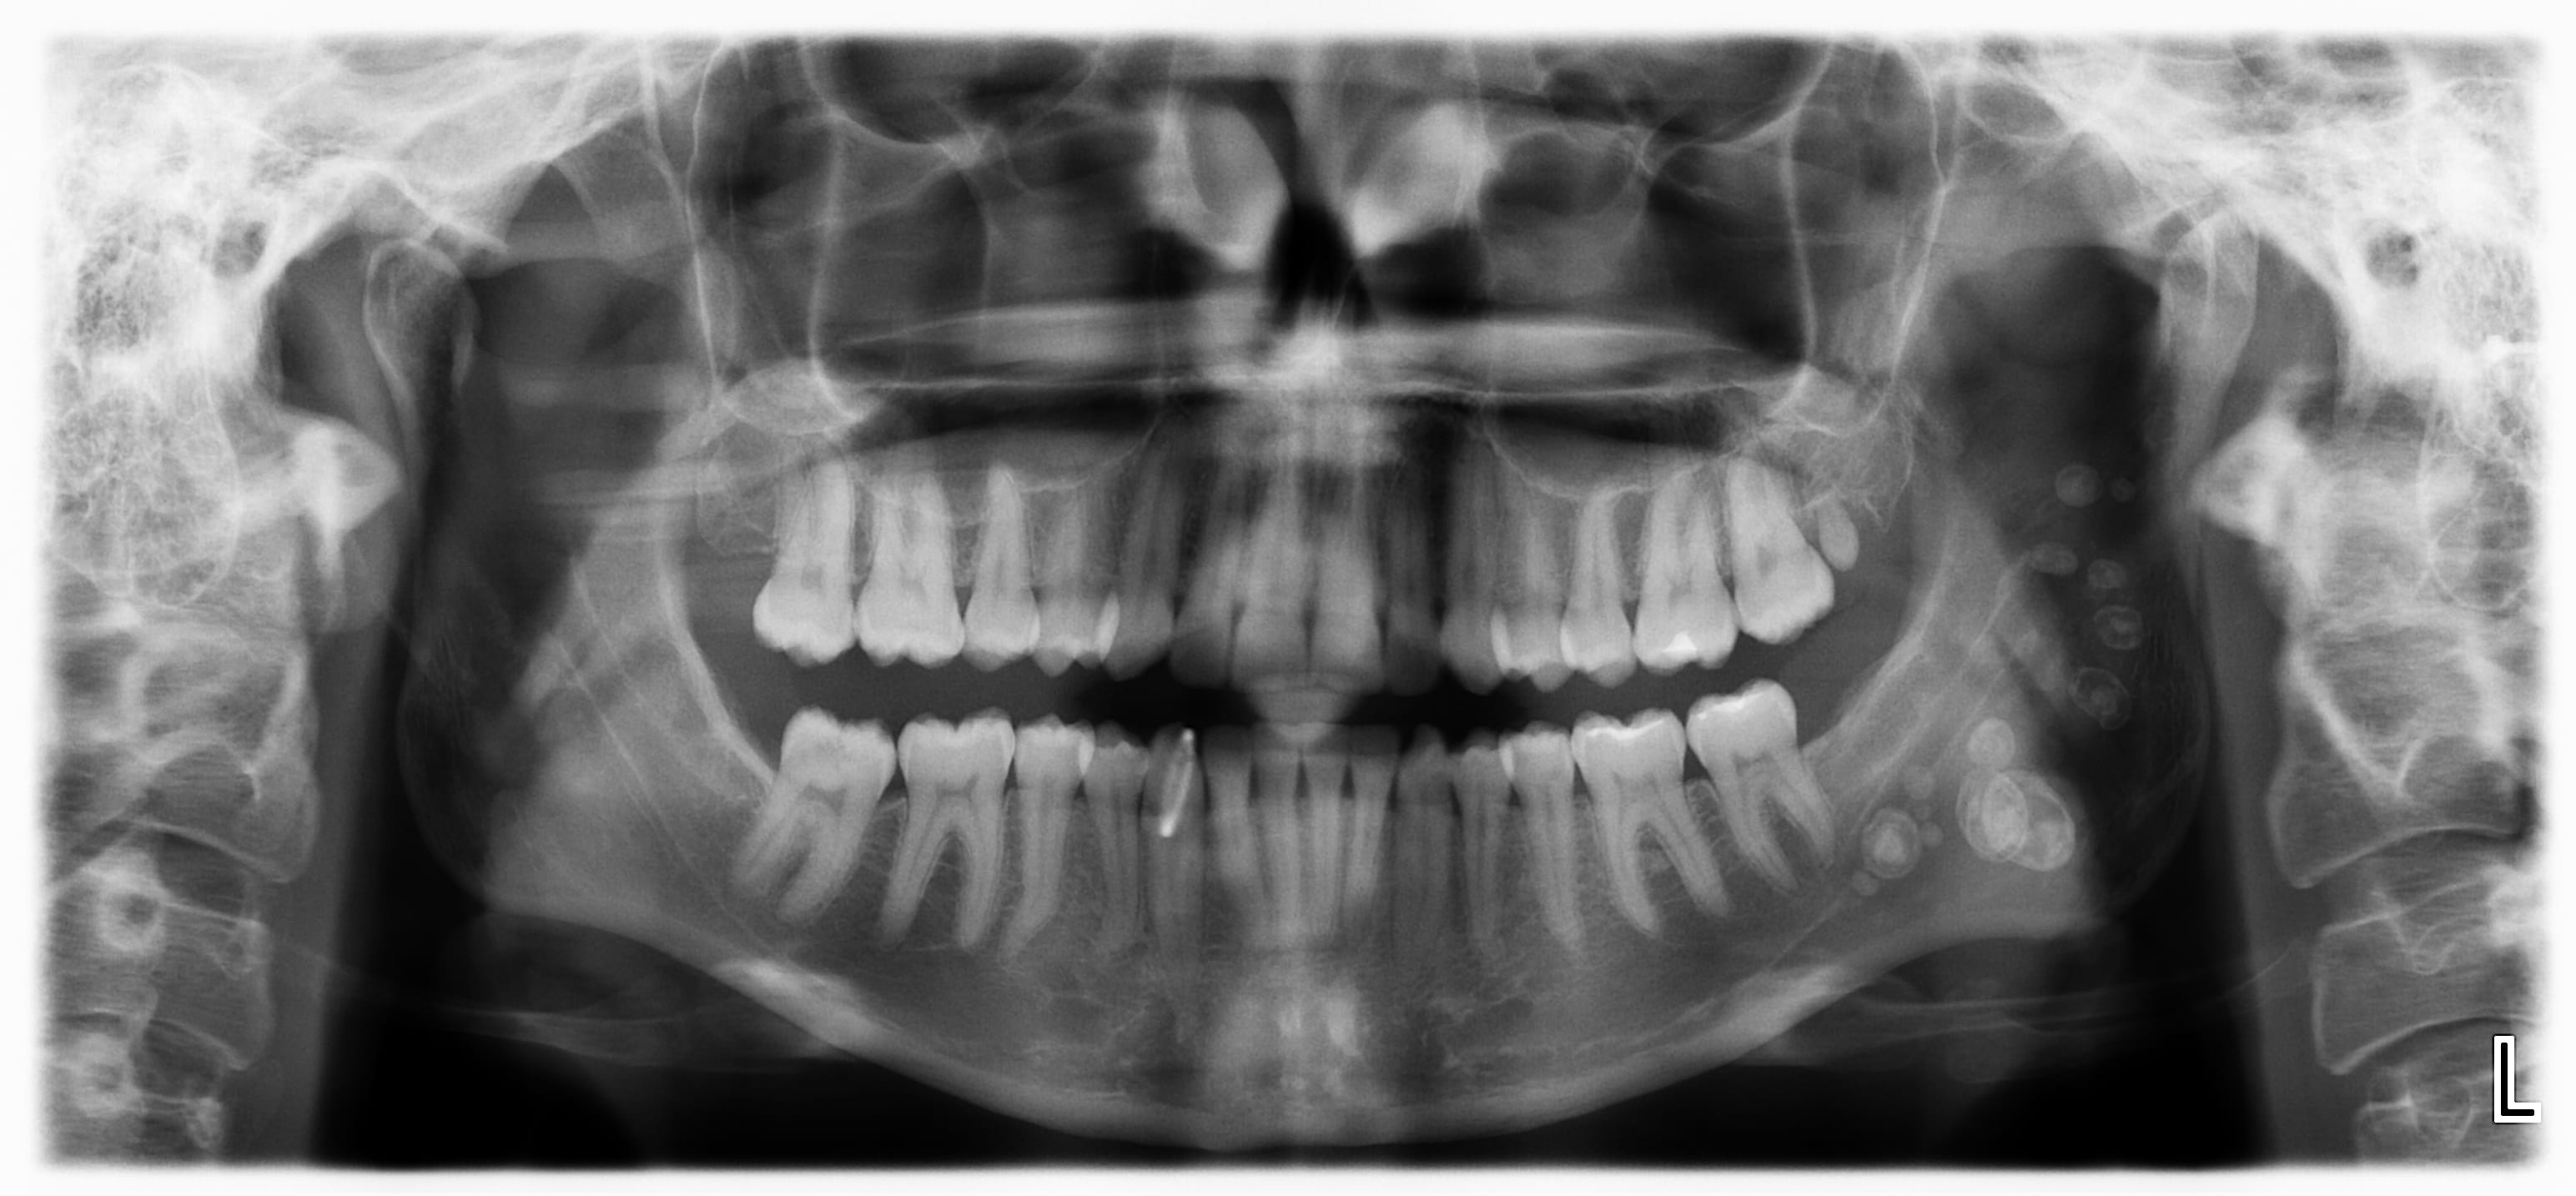

découverte fortuite à la pano.

Hyperodontie?

amha c'est plutôt des calculs salivaires parotidiens....

je la revois dans 3 mois car etudie à londres

je demanderai une echographie